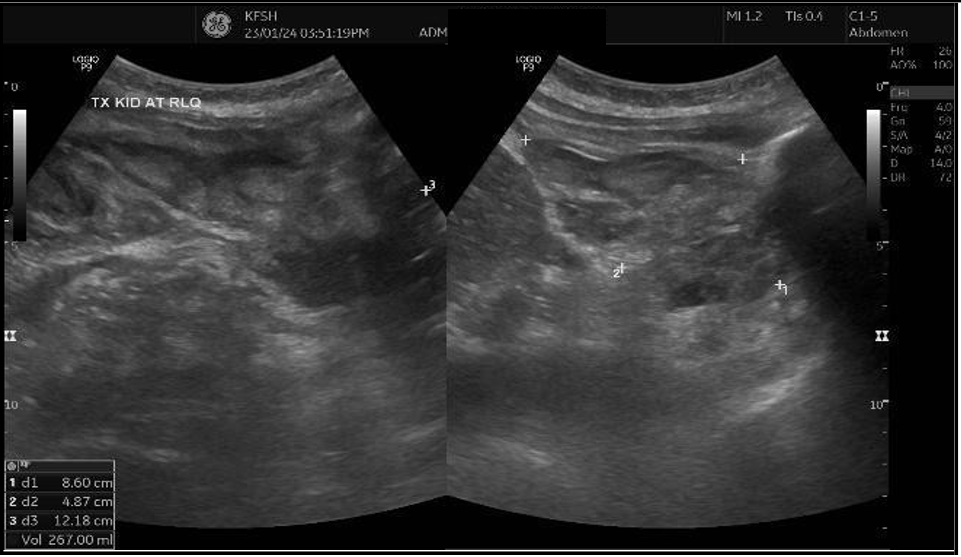

Follow-up graft ultrasound revealed a marked increase in peri-graft fluid collection, expanding from 74 mL to 267 mL, suggestive of a postoperative hematoma or lymphocele [Figure 2]. Following surgical team consultation, the patient was admitted for blood pressure control, red blood cell transfusion, and close monitoring of renal function. After receiving four units of packed red blood cells, her hemoglobin stabilized at 7.4 g/dL, but creatinine continued to rise, reaching 155 µmol/L, with a urine albumin-to-creatinine ratio (ACR) of 762 mg/g.

(A)

(B)

Figure 2: (A) Ultrasound Doppler of renal transplant showing perigraft heterogeneous fluid collection measuring 4.0 × 5.2 × 6.6 cm (74 mL) (B) Left lower quadrant collection measuring 8.6 × 4.8 × 12 cm (267 mL).